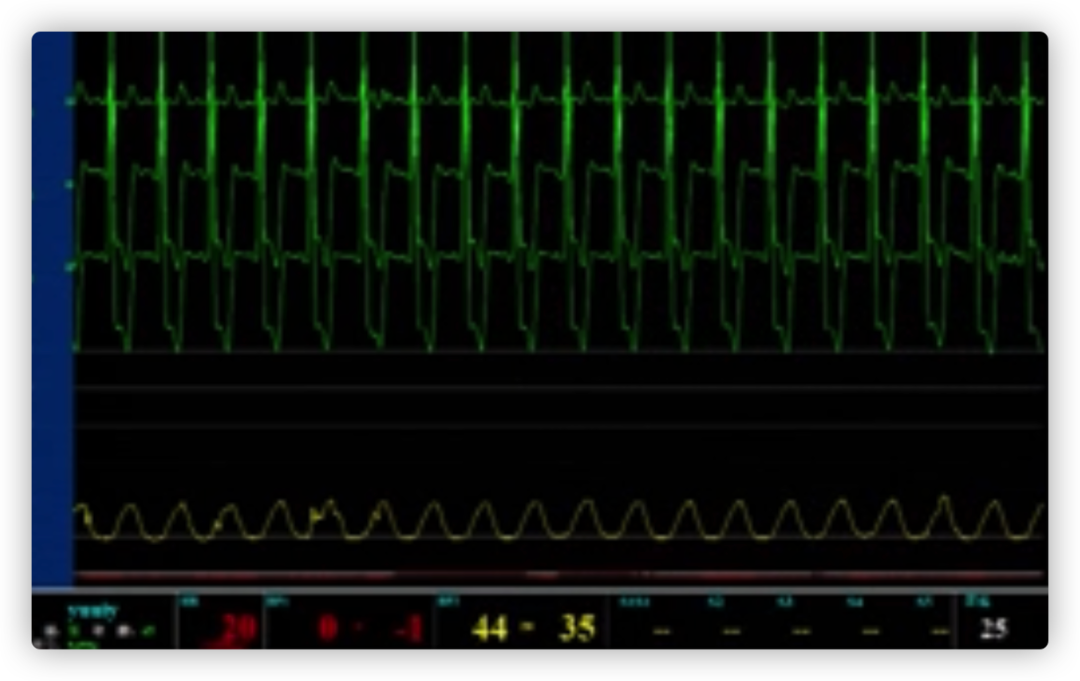

ECG术前

ECG术后即刻

ECG出院时